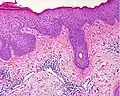

In der histologischen (lichtmikroskopischen) Untersuchung einer Gewebeprobe aus erkrankter Haut weist das Ekzem die Merkmale einer spongiotischen Dermatitis auf. Analog zum klinischen Bild zeigt sich ein charakteristischer Verlauf der Veränderungen:

Akute Phase: In der Oberhaut (Epidermis) zeigt sich eine Gefügelockerung durch ein interzelluläres Ödem (Spongiose), das bei starker Ausprägung zur Ausbildung von kleinen, aber auch größeren Blasen (Vesikel bzw. Bullae) führen kann.

Als Kratzeffekt besteht eine überschießende und eventuell auch gestörte Verhornung (Hyperkeratose bzw. Parakeratose) mit überliegender Schuppenkruste (parakeratotische Hornschicht mit eingeschlossenen Serumresten). Auch die oberen Anteile der Lederhaut (Dermis) sind durch ein Ödem gelockert, hier finden sich außerdem weitgestellte kleine Blutgefäße (Kapillaren). Um diese Gefäße bilden sich Ansammlungen aus Entzündungszellen, die sich hauptsächlich aus Lymphozyten und Histiozyten, nicht selten auch eosinophilen Granulozyten (Untergruppen der weißen Blutkörperchen) zusammensetzen. Lymphozyten wandern teilweise auch in die Epidermis ein (lymphozytäre Exozytose).

Als Reaktion auf den anhaltenden Entzündungsreiz und juckreizbedingtes Kratzen kommt es in der Folge zur Verbreiterung der Epidermis (Akanthose) mit Rückgang der Spongiose. Anfangs eventuell vorhandene größere Blasen gehen zurück, und es verbleiben nurmehr kleine Bläschen. Zumeist besteht jetzt eine ausgedehnte Parakeratose, und im Randbereich oberflächlicher epidermaler Defekte (Erosionen) können auch neutrophile Granulozyten (Untergruppe der weißen Blutkörperchen) in der Epidermis zu sehen sein. Dieses Zwischenstadium wird gelegentlich auch als subakute Phase bezeichnet.

Chronische Phase: es überwiegen die Zeichen der chronischen mechanischen Irritation mit Lichenifikation: epidermal zeigt sich eine deutliche Akanthose mit Verbreiterung der Granularzellschicht (Hypergranulose) und Hyperkeratose. Die Spongiose geht weiter zurück und kann in diesem Stadium nur noch sehr schwach ausgeprägt sein. Das der Epidermis unmittelbar unterliegende Bindegewebe der oberen Dermis (Stratum papillare) zeigt eine Vermehrung von Kollagenfasern (Fibrose), die senkrecht zur Epidermis ausgerichtet sind.[5]

-

Spongiose: Gefügelockerung der Epidermis mit sichtbaren Spalten zwischen den einzelnen Zellen durch interzelluläres Ödem -

Vesikelbildung: bei starker Spongiose lösen sich die Zellen voneinander und es bilden sich kleine Bläschen

Hyperkeratose: der Epidermis aufgelagert besteht eine verbreiterte Hornschicht. In der Dermis Kapillaren mit umliegenden Entzündungszellen

Parakeratose: die Hornschicht enthält Reste von Zellkernen als Zeichen der gestörten Verhornung